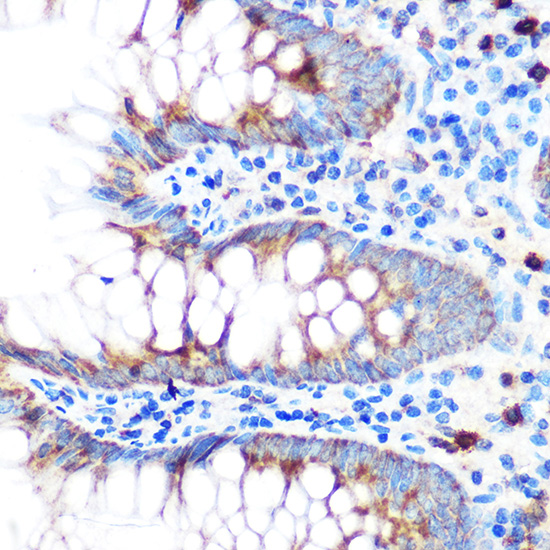

Immunohistochemistry of paraffin-embedded human appendix using GPX4 Rabbit pAb.